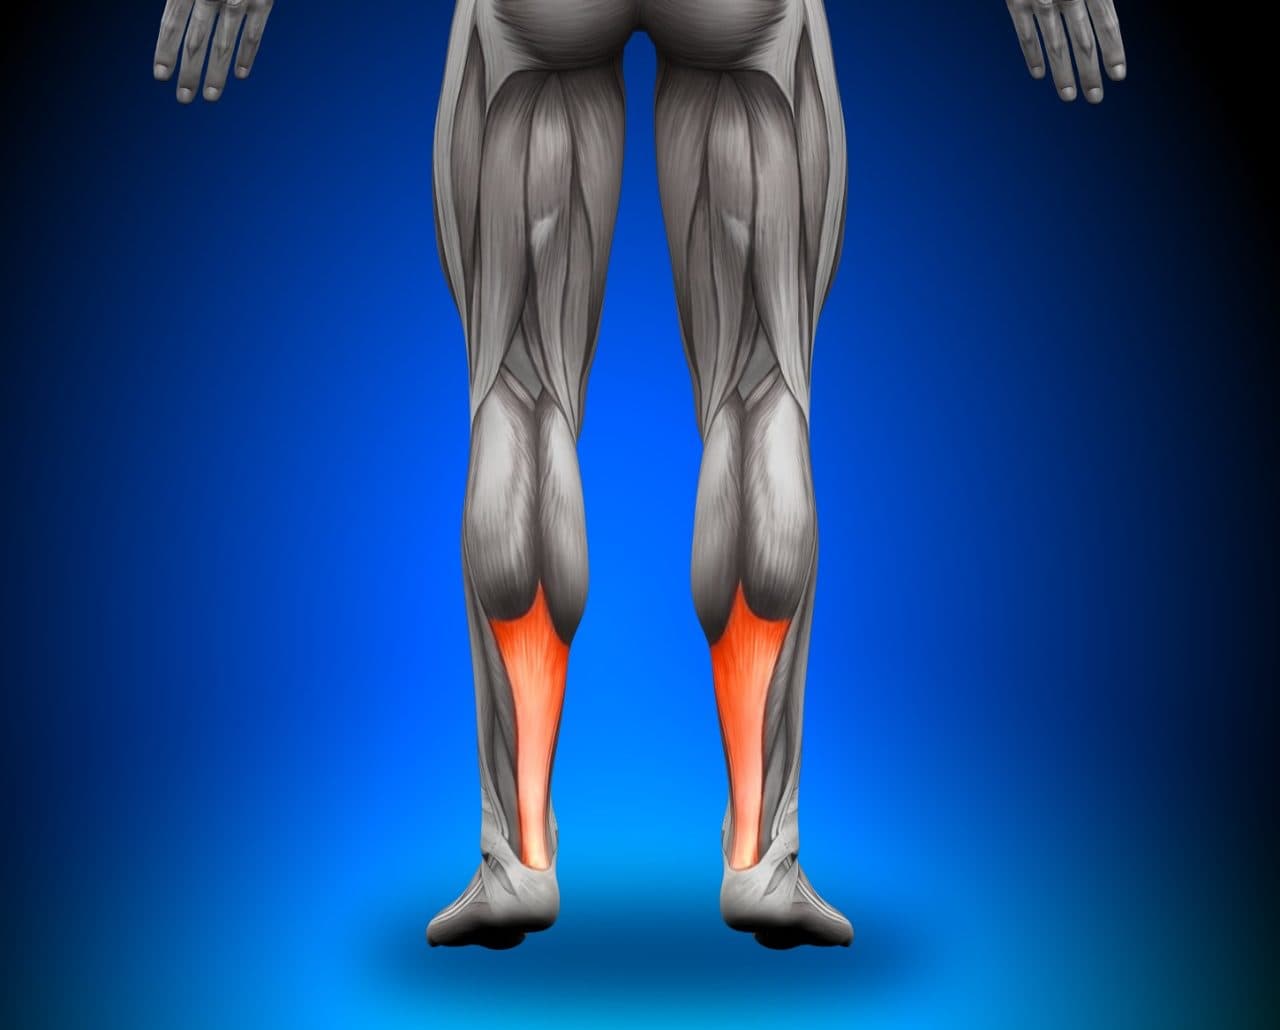

A tendinite de Aquiles é aquela dor chata que aparece na parte de trás do seu calcanhar, bem ali onde o músculo da panturrilha se liga ao osso do pé. Sabe, é uma inflamação desse tendão forte que usamos para correr, pular e até para andar. Quando exigimos demais dele, ou quando ele já está cansado e fraco, o problema aparece.

Quando falamos de fortalecimento, não estamos falando de levantar pesos enormes de cara. Começamos com exercícios mais leves e focados, que visam principalmente a panturrilha (músculo gastrocnêmio e sóleo). Eles são os grandes responsáveis por fazer o movimento do nosso pé lá atrás. Exercícios como elevação de calcanhar, tanto com os joelhos esticados quanto dobrados, são essenciais. Fazer de forma controlada e com atenção à sua resposta corporal é fundamental para não sobrecarregar ainda mais o tendão que já está sensível.